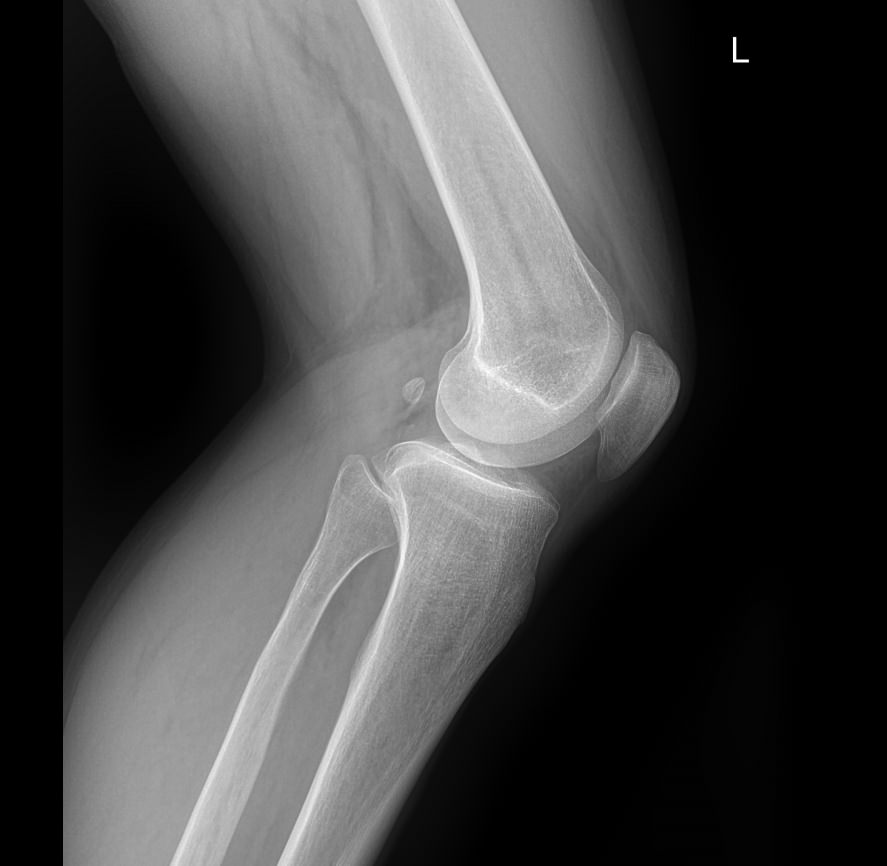

Назад Рентген обоих коленных суставов

Что покажет рентген обоих коленных суставов в одной проекции

В протоколе у каждого сустава описывается:

• Состояние мягких тканей;

• Суставная щель ― в норме, расширена, сужена, затемнена, имеет дополнительные включения;

• Состояние суставных  поверхностей и их соответствие друг другу ― несоответствие говорит о вывихе;

• Положение надколенника ― обычное или нет;

• Состояние костной ткани и надкостницы ― могут быть обнаружены участки разрежения, размягчения или других патологических процессов, а также свежие и сросшиеся переломы.